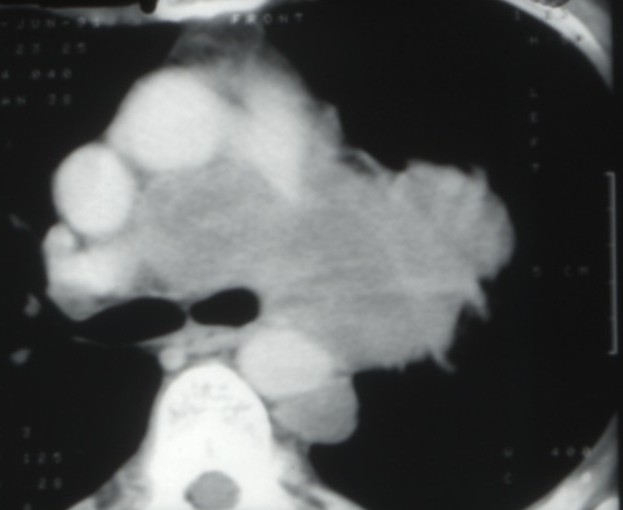

Cancers bronchiques